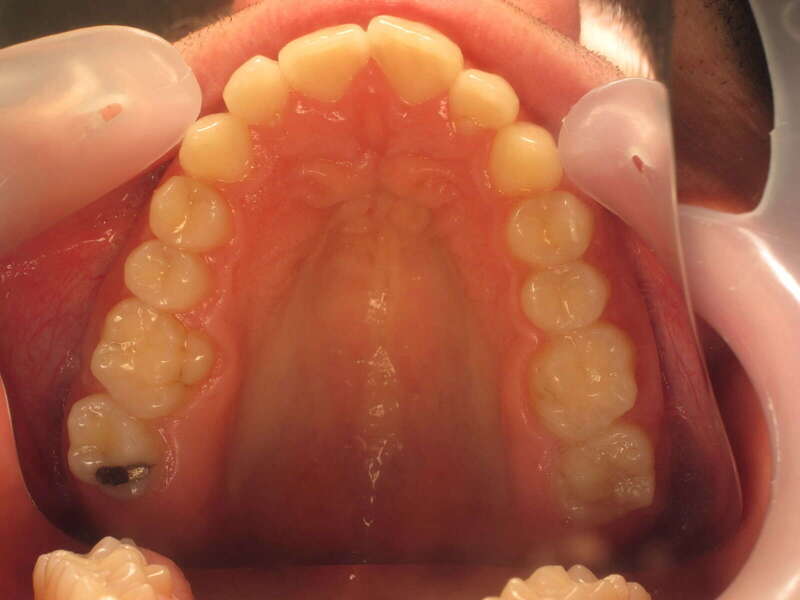

Cas n°1 traité par aligneurs (interception) - enfant

Ce cas d’interception chez un enfant de 8 ans démontre l'efficacité des aligneurs pour corriger des troubles fonctionnels précoces. Le diagnostic présentait des inversions d'articulé provoquant une déviation de la mandibule vers la gauche et un décalage des milieux.

Grâce à une coopération exemplaire et un traitement totalement indolore, l'expansion de l'arcade a permis de recentrer la mâchoire. Cette intervention a littéralement remis la croissance sur les rails, neutralisant le risque d'asymétrie faciale squelettique.

• Correction fonctionnelle : Recentrage immédiat de la mandibule et des milieux inter-incisifs.

• Prévention : Création d'un environnement favorable pour les dents définitives à venir.

• Bien-être : Approche douce respectant le confort de l'enfant.

C'est une étape fondamentale qui simplifie l'avenir orthodontique du patient tout en garantissant un développement facial harmonieux.

Avant

Après